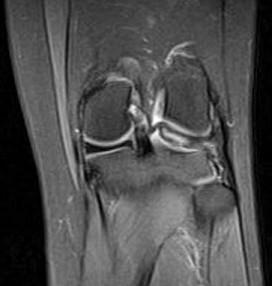

问题 男,16岁,左膝关节有过外伤,现肿痛,有膝关节弹响,请结合MRI检查,选出最可能的诊断 ( )

选项 A、关节结核 B、风湿关节炎 C、滑膜炎 D、半月板撕裂 E、化脓性关节炎

答案 D